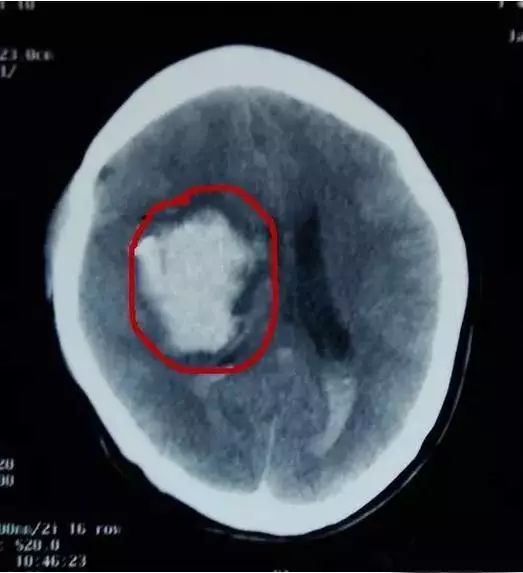

经医生诊断后得知:两个婴儿均为颅内出血且因失血过多出现贫血症状,

最后紧急做了开颅手术,才保住两个宝宝的性命!

迟发性外伤性颅内出血,以3岁以下的幼儿居多,6小时内的发生率较高。迟发性外伤性颅内出血并不在事发当时就表现出异样,因而往往导致就诊不及时,造成严重后果。

宝妈们就要怀疑,是否是迟发性外伤性颅内出血。出现这些症状,一定要及时到正规医院做相关检查,如头颅CT等。宝宝脑外伤24小时内观察很重要,尤其是外观不明显的脑外伤。